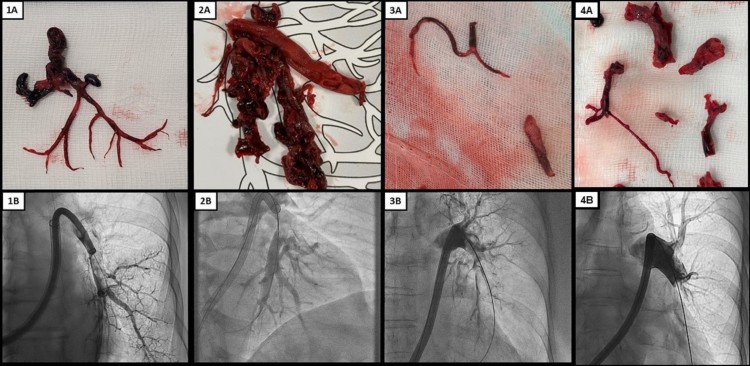

Resultados: Desde el inicio del programa de TMP hemos valorado 143 casos, de los que finalmente se ha realizado TMP en 42 (29%). Hemos identificado 38 casos de TEP aguda (91%) y 4 casos de TEP subaguda (9%). Seleccionamos pacientes con TEP de alto riesgo y contraindicación para fibrinolisis y pacientes con TEP de riesgo intermedio-alto con peor pronóstico definido por una puntuación en la escala de BOVA #1 4, que podrían beneficiarse de una terapia más agresiva inicial. Hasta la fecha, todos los procedimientos que hemos llevado a cabo han sido exitosos, considerando éxito del procedimiento como la extracción de trombo asociada a una mejoría de la situación hemodinámica y respiratoria. En cuanto a la seguridad del procedimiento, no se han producido complicaciones del acceso vascular ni perforaciones de estructuras cardiacas. Presentamos 4 casos de TEP subaguda tratada con TMP. Las características de los pacientes se encuentran en la tabla. Estos casos muestran la presentación característica de la TEP subaguda: disnea de semanas de evolución seguida de deterioro brusco, con presiones pulmonares más elevadas, y la presencia de auténticos moldes trombóticos organizados de gran tamaño que se mezclan con trombos frescos agudos, pudiendo ser ambos extraídos eficazmente con la TMP en un procedimiento algo más largo que el de la TEP aguda. Esto se tradujo en una mejoría inmediata hemodinámica y funcional, sin complicaciones.

Imágenes macroscópicas de los moldes de tromboembolia pulmonar subaguda de cada paciente (paneles superiores) y su equivalente angiográfico (paneles inferiores). Paciente 1: 1A y 1B, paciente 2: 2A y 2B, paciente 3: 3A y 3B.